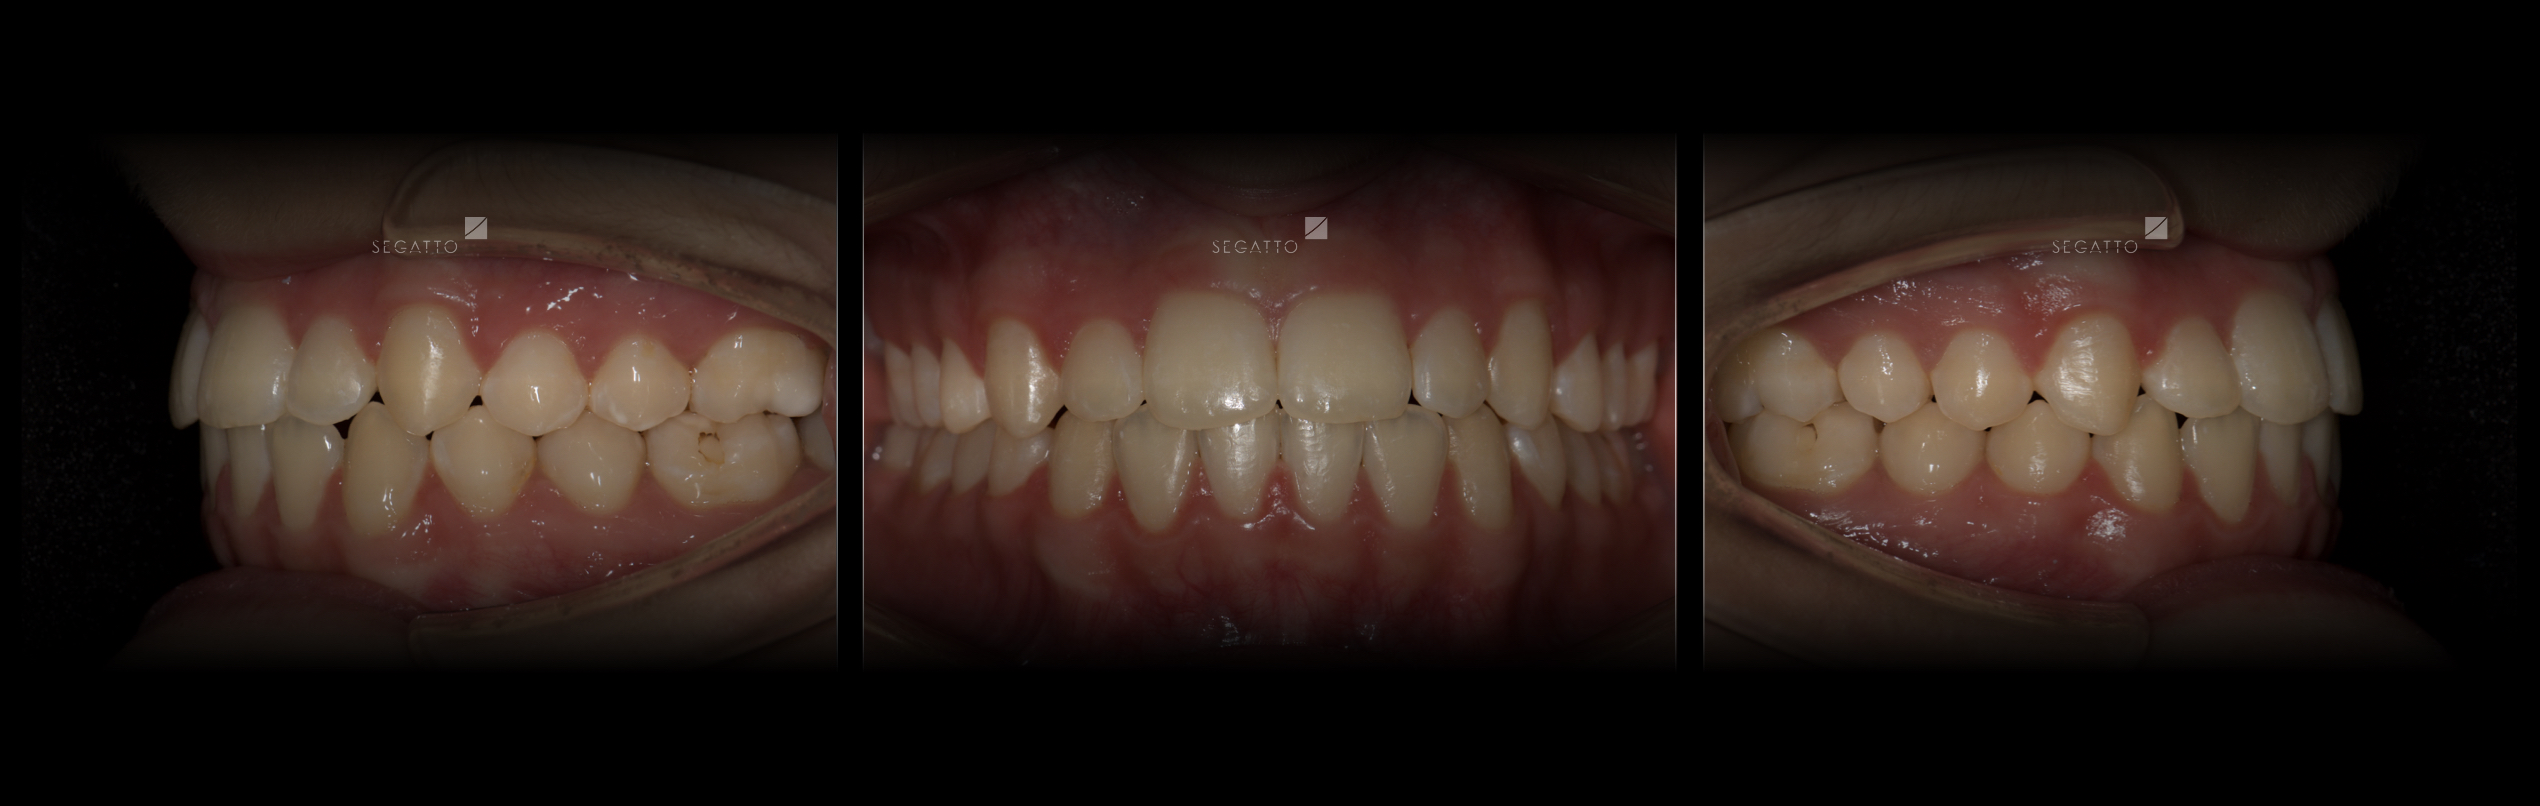

Orthodontics

Cases